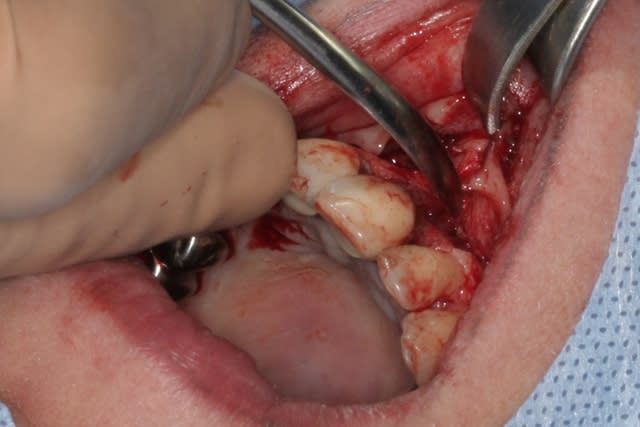

cet implant est une merveille!!!

connexion au top, pièces prothétiques aussi, facilité de pose incroyable...

tien, ce matin, extraction de 24/25, curetage méticuleux, forage, comblement du gap, pose des 2 implants qui se sont bloqués à 50Ncm au CA sur les 3 ou 4 mm apicaux, pose des vis de cicat, sutures...35min....tranquille...

désolé, la pano est un poil déformée (la patiente à du bouger...)